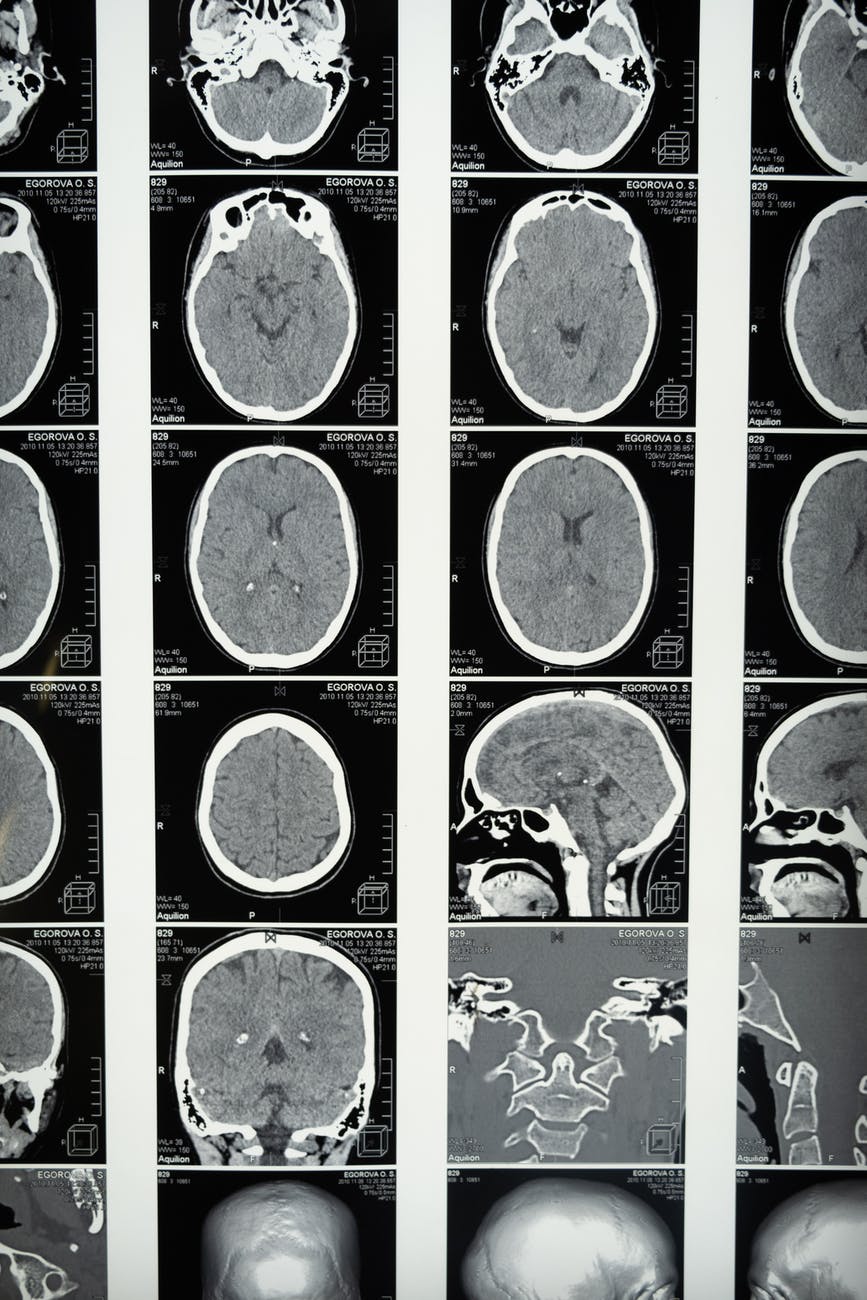

La resonancia magnética nuclear ( RMN ), o imagen por resonancia magnética nuclear ( NMRI ), es principalmente una técnica de imagen médica que se usa más comúnmente en radiología para visualizar la estructura interna y la función del cuerpo. La resonancia magnética proporciona un contraste mucho mayor entre los diferentes tejidos blandos del cuerpo que la tomografía computarizada (TC), lo que la hace especialmente útil en imágenes neurológicas (cerebro), musculoesqueléticas, cardiovasculares y oncológicas (cáncer). A diferencia de la TC, no utiliza radiación ionizante, pero utiliza un campo magnético potente para alinear la magnetización nuclear de (normalmente) átomos de hidrógeno en el agua del cuerpo. Los campos de radiofrecuencia (RF) se utilizan para alterar sistemáticamente la alineación de esta magnetización, lo que hace que los núcleos de hidrógeno produzcan un campo magnético giratorio detectable por el escáner. Esta señal puede ser manipulada por campos magnéticos adicionales para generar suficiente información para construir una imagen del cuerpo.:36